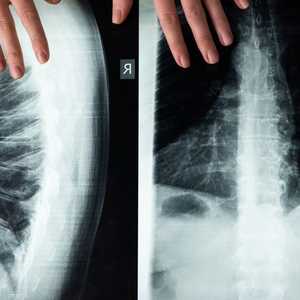

والمقصود بمنطقة "فوق الجافية" (epidural space)؛ هو الحيز التشريحي في العمود الفقري الذي يقع في الجزء الخارجي من القناة النخاعية.

وفي هذا الإنجاز الطبي الحديث، تم إدخال جهاز على شكل مجداف، إلى جسم المريض، من أجل تحفيز إشارات الأعصاب حتى يصبح الشخص قادرا على المشي.

وقام الباحثون بربط أسلاك هذا القطب الكهربائي، بمحفز عصبي تمت زراعته تحت الجلد في منطقة البطن.